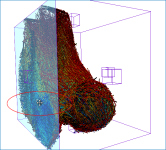

Screen capture of the completed tutorial

Below are some examples of vector field-based anisotropy maps shown from different aspects. The top row includes visualizations of anisotropy magnitude, while the bottom row shows vector fields colored by orientation. The pair of images on the right show maps that are clipped.

The 3D vector field-based anisotropy map appears in the 3D view at the default settings, with the vectors corresponding to the highest surface anisotropy colored yellow and those corresponding to the lowest, or isotropy, colored blue.

Information and settings related to the selected vector-based field appear in the bottom section of the Data Properties and Settings panel.